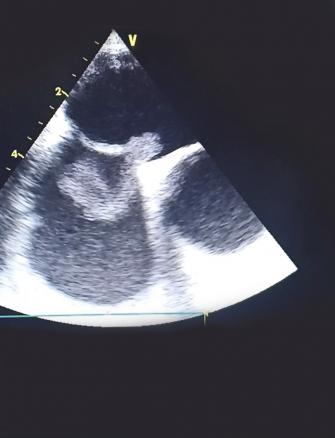

Cet homme de 37 ans était hospitalisé pour une hémiplégie gauche, 40 jours après ostéosynthèse d’une fracture du tibia droit. Son état hémodynamique et respiratoire était stable lors de son admission, avec des signes de thrombophlébite du membre inférieur droit et un rythme régulier sinusal à l’électrocardiogramme. La tomodensitométrie cérébrale montrait une plage ischémique temporo-pariétale droite. L’échocardiographie visualisait un thrombus mobile enclavé dans le foramen ovale perméable. Le patient était mis sous traitement anticoagulant ; une thrombectomie chirurgicale était réalisée avec fermeture du foramen ovale. Les suites opératoires étaient simples.

L’embolie paradoxale à travers un foramen ovale perméable est une cause rare d’accident vasculaire cérébral ischémique. Elle est due à l’embolisation systémique d’un caillot provenant de la circulation veineuse à travers le foramen ovale. Le diagnostic est posé devant la présence d’une thrombose veineuse, une preuve d’embolisation systémique et la démonstration échocardiographique d’une communication anormale entre les circulations droite et gauche.

La visualisation d’un thrombus enclavé dans le foramen ovale est exceptionnelle et augmente la mortalité et le taux de récidive ischémique liée à cette pathologie.1, 2